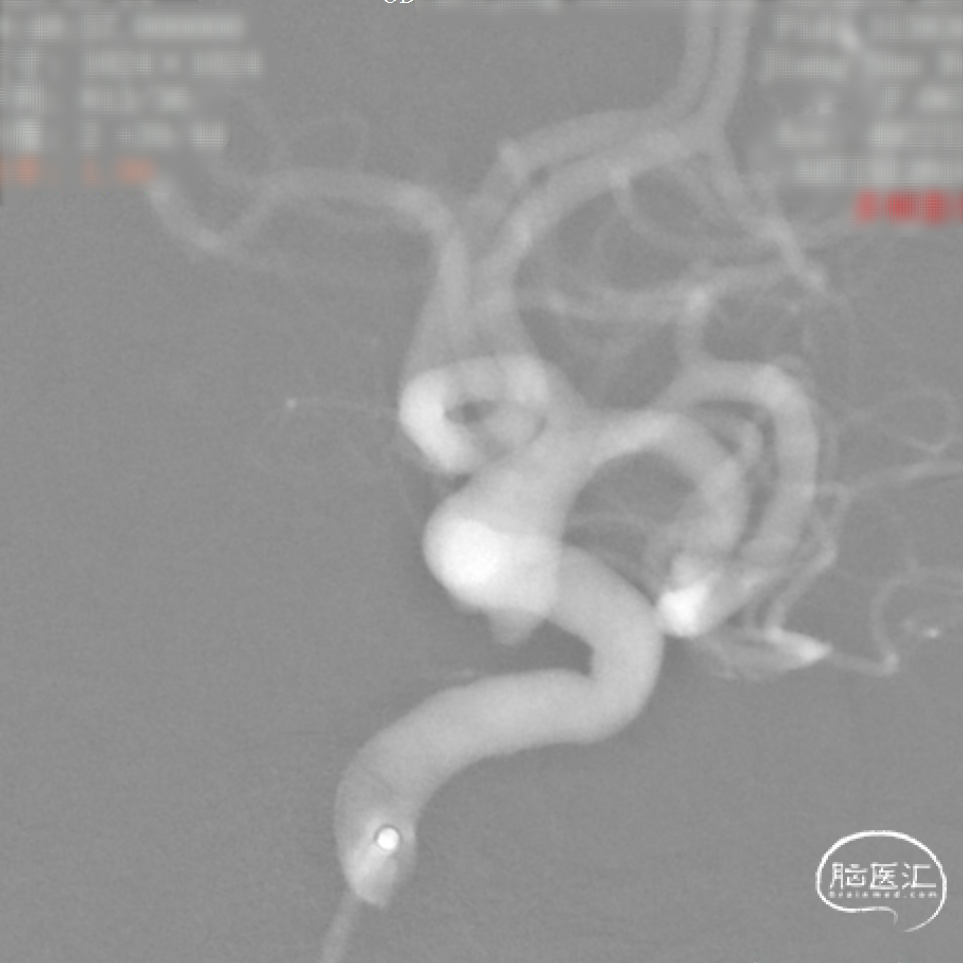

CTA:右侧颈内动脉C7段动脉瘤。

老年女性患者,检查发现右侧颈内动脉C7段大动脉瘤,动脉瘤直径大于10mm,形态不规则,宽颈,手术指征明确,既往高血压、肿瘤病史,首选微创介入手术,术中造影证实动脉瘤直径大于10mm,绝对宽颈,形态不规则,局部仔瘤改变,右侧脉络膜前动脉从瘤体发出;微创介入血流导向装置是较优选择。

工作角度:

大动脉瘤的微创介入栓塞治疗存在需要支架辅助,瘤颈处理困难、复发率高、费用高等难点;血流导向密网支架置入是较优选择,操作相对简单,不用填塞弹簧圈,完整覆盖瘤颈,远期明显降低再复发概率。本病例为右侧颈内动脉C7段累及脉络膜前动脉的大动脉瘤,该部位解剖结构复杂,周围血管分支多,在操作过程中要避免损伤正常血管,否则会引发严重脑缺血事件;其次,动脉瘤与脉络膜前动脉关系密切,既要处理好动脉瘤,又要保证脉络膜前动脉的血供不受影响,这对手术操作精度要求较高;再者,瘤颈的处理较为棘手,瘤颈较宽,传统弹簧圈栓塞难以达到理想效果,且容易复发。血流导向密网支架置入可解决这些问题,术前需借助3D-DSA,全面评估动脉瘤大小、形态、瘤颈宽度、与周围血管关系,制定精准手术方案。操作时,微导管的到位是关键一步,要在路径图引导下,小心、轻柔操作,避免刺激血管引发痉挛或动脉瘤破裂。释放支架过程中,要注意关注支架位置和贴壁情况。释放后要通过多角度造影,确认支架完全覆盖瘤颈,且支架内血流通畅,分支血管未受影响。同时,术后要密切观察患者神经功能变化,预防血栓形成、血管痉挛等并发症,及时给予抗血小板、解痉等药物治疗。

Surpass Evolve血流导向密网支架是专为颅内动脉瘤介入治疗设计的血流导向装置,采用钴铬合金编织网,金属覆盖率可达30-35%;头端易打开,具备优异的贴壁性,通过性优越,适合迂曲血管路径;多规格可选;适用于复杂型(大型、巨大型、梭形或宽颈)颅内动脉瘤。